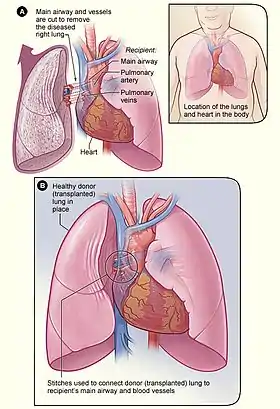

Illustration showing the process of a lung transplant. In figure A, the airway and blood vessels between a recipient’s diseased right lung and heart are cut. The inset image shows the location of the lungs and heart in the body. In figure B, a healthy donor lung is stitched to the recipient’s blood vessels and airway. | |